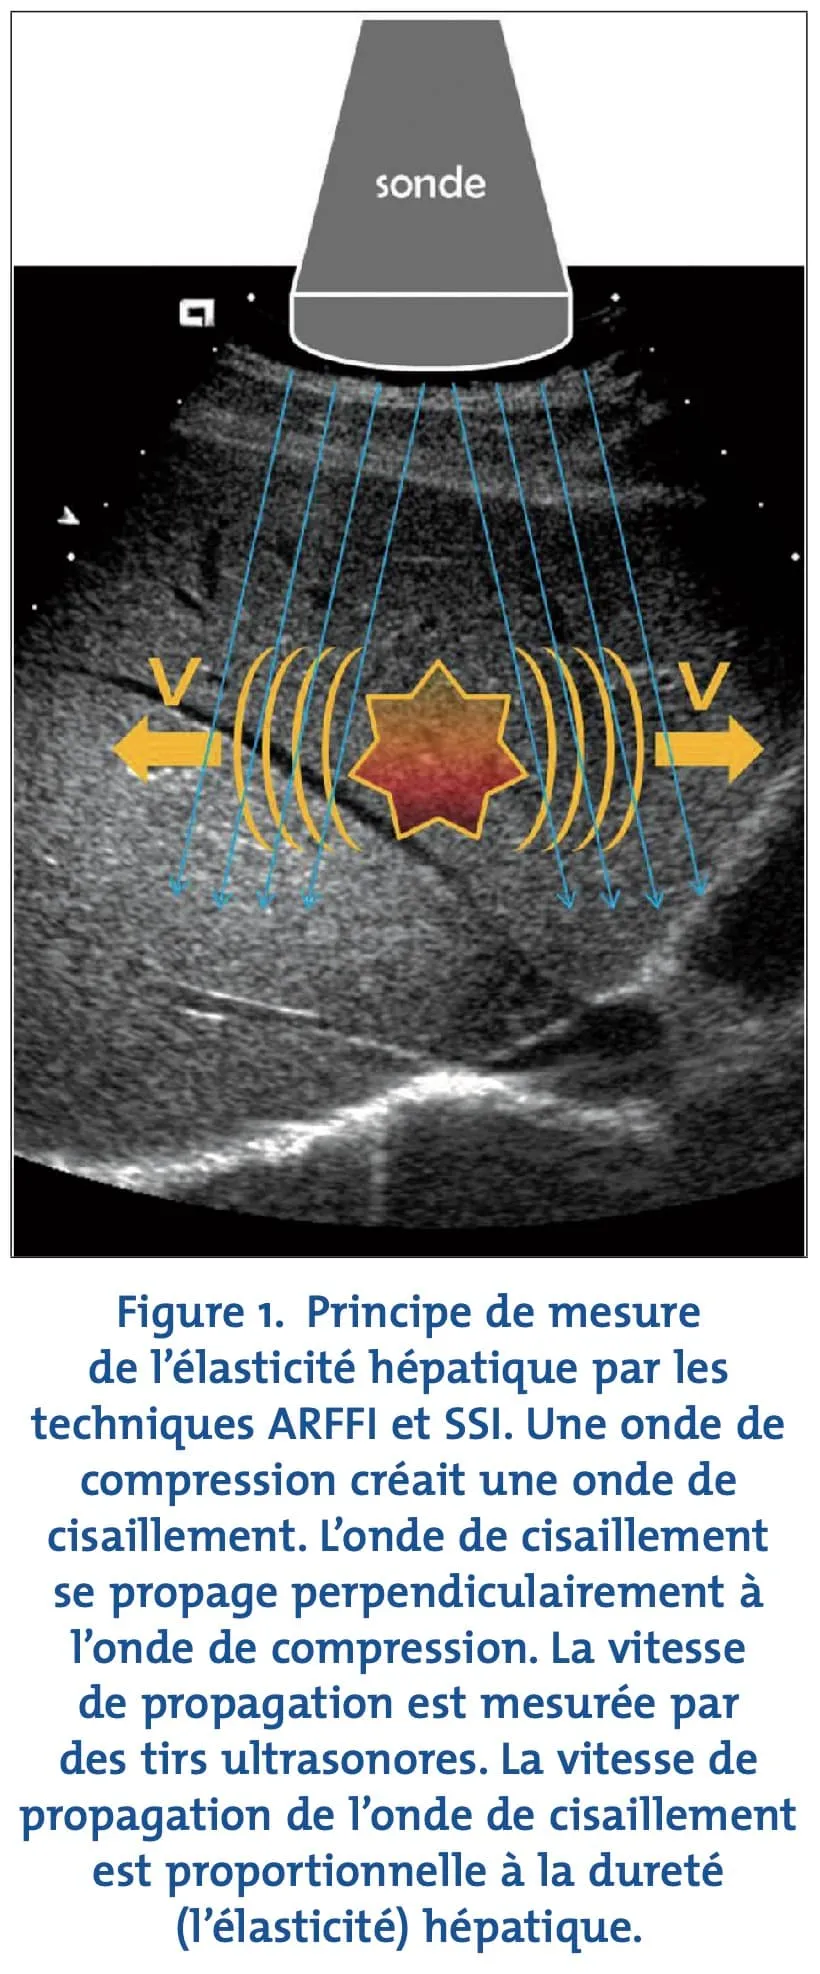

Élastographie hépatique — Évaluation de la fibrose hépatique

L’élastographie hépatique est l’imagerie de la fibrose hépatique en utilisant les ondes de cisaillement pour une analyse reproductible et non invasive.

Nos machines utilisent les ondes de cisaillement pour mesurer cette fibrose de façon non invasive, quantifiée très précisément et de façon reproductible. Contrairement aux autres techniques d’élastographie ultrasonore, les ondes de cisaillement permettent une mesure dont la précision et la reproductibilité sont indépendantes de l’opérateur.